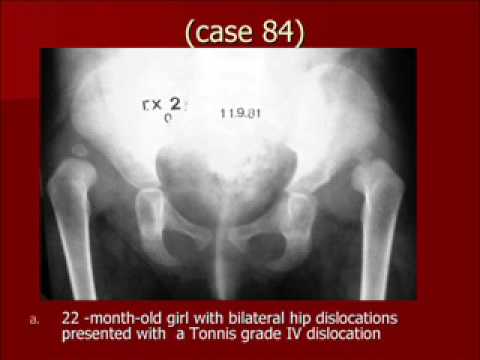

CHIROPRACTIC MANAGEMENT OF PATIENTS WITH BILATERAL CONGENITAL ...

CHIROPRACTIC MANAGEMENT OF PATIENTS WITH BILATERAL CONGENITAL HIP DISLOCATION WITH CHRONIC LOW BACK AND LEG PAIN Francisco Dı´ez, DCa ABSTRACT Objective: To discuss conservative methods for treating patients with chronic low back and leg pain associated with the ... Fetch Document